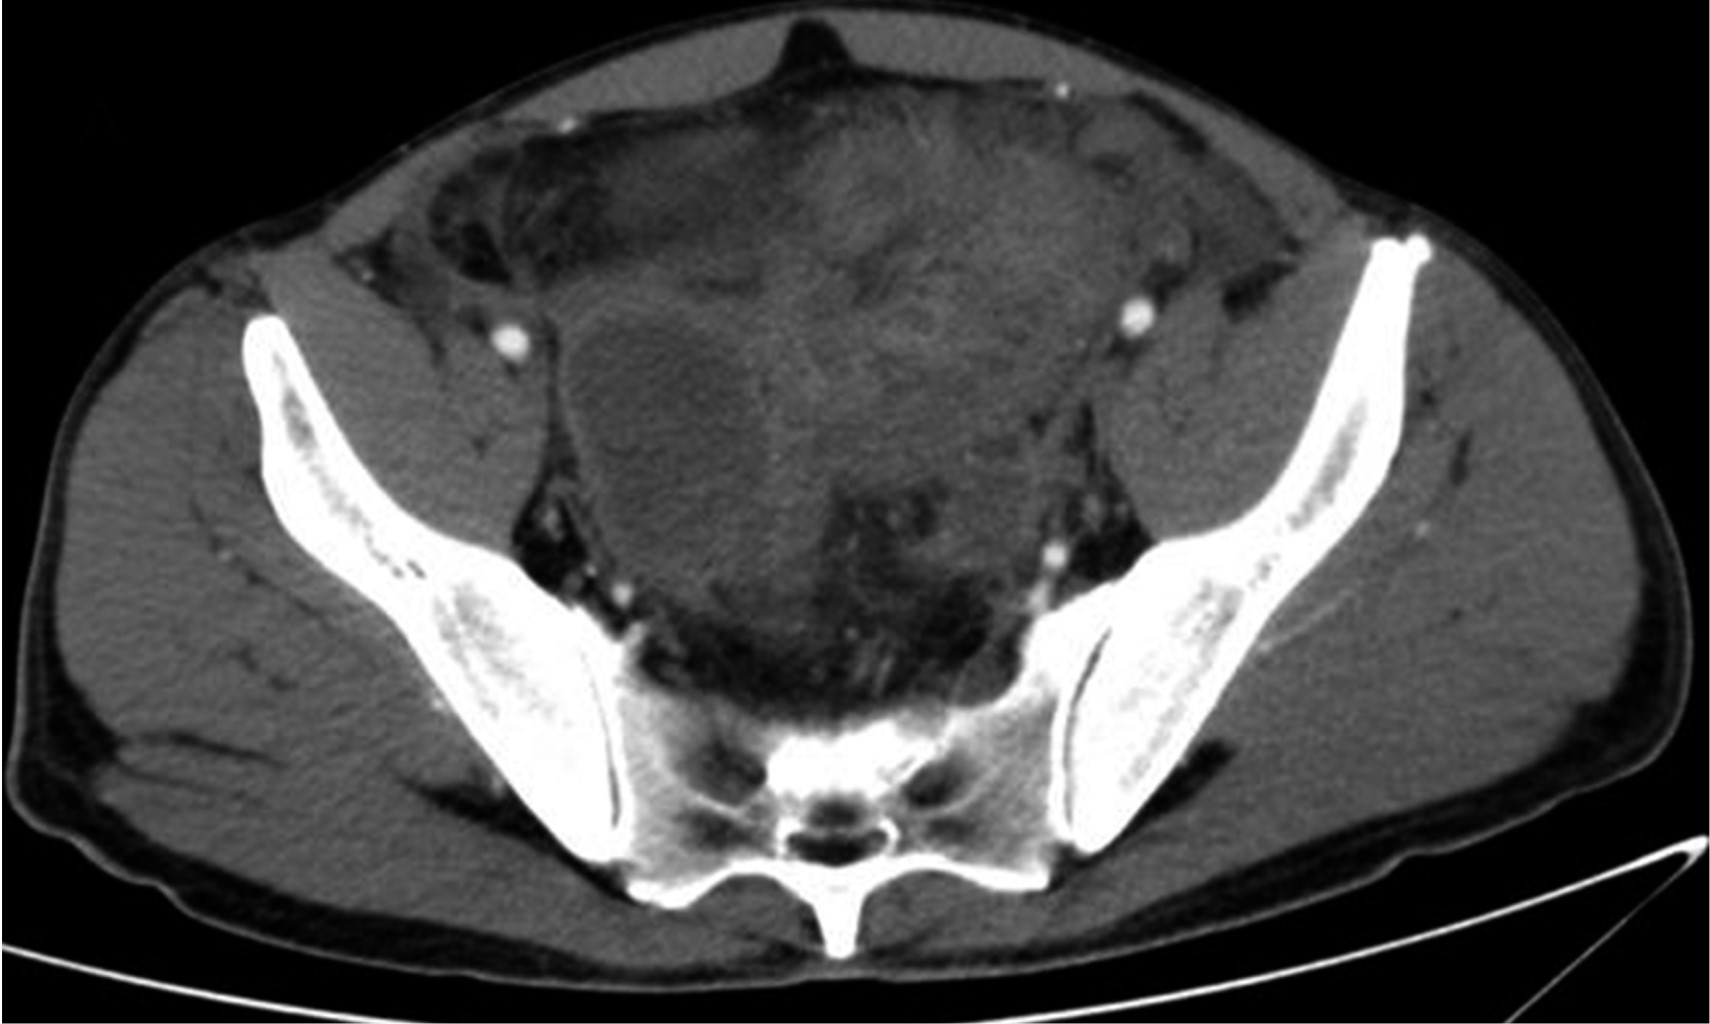

The CT scan of abdomen and pelvis with IV contrast showed free fluid in the right parieto-colic, intestinal interloop and peri-cecal slides. The cecal appendix with a diameter of 14 mm and thickening and enhancement of its wall was seen. A supra-vesical collection with extension to the right iliac fossa measuring 55 × 75 × 41 mm with a calculated volume of 88 cm3 (Figure 1) and another in the cul-de-sac with extension to the left iliac fossa measuring 60 × 57 × 70 mm with a volume of 125 cm3 were observed. Ultrasound-guided puncture with tomographic control of both collections was decided to perform (Figure 2), draining 70 and 120 cm3 of purulent fluid, respectively. Two Dawson Mueller® 10.2 Fr drains were left, one in the right iliac fossa and the other in the cul-de-sac zone. Broad spectrum antimicrobial management was started with meropenem 1 g iv every eight hours and vancomycin 1 g iv every 12 hours. He was left fasting for two days and parenteral nutritional support was started for three days with Oliclinomel® solution. The aerobic culture grew Streptococcus constellatus sensitive to ertapenem, so antimicrobial coverage was changed to ertapenem 1 g iv every 24 hours and vancomycin. The patient remained clinically stable, with no evidence of systemic inflammatory response and a progressive decrease in abdominal pain intensity. A control CT scan on his third hospital day (Figure 3) showed a significant decrease of fluid inside the collections. The right drain was removed on fourth day, with a total output of 10 cm3. Inflammatory markers showed a progressive decrease during his hospital stay. Final lab test results showed a white blood cell count of 9.9 10?3/μl, segmented neutrophils 67%, band forms 0% and a CRP of 4.05 mg/dl. The left drain was removed prior to hospital discharge on the ninth day of stay with a total output of 82 cm3. No interval appendectomy was performed during his follow-up because, based on age, history and imaging studies at diagnosis, the probability of neoplasia was considered low according to existing literature recommendations.

Figure 1